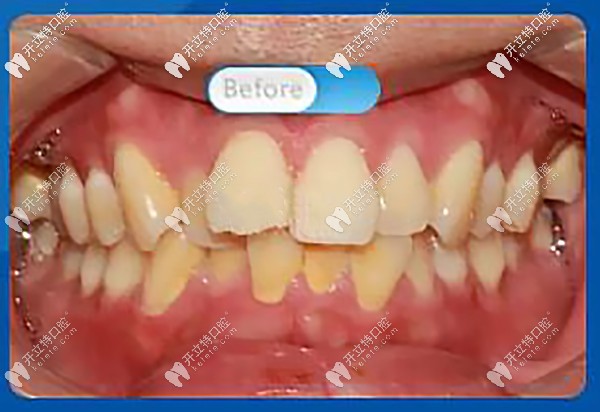

托槽矯正前,正面看牙齒屬于重度擁擠,微笑時,明顯看到前牙凸出,凸嘴齙牙明顯

正面看牙齒屬于重度擁擠

醫(yī)生:“從口內(nèi)正面照可以看到上牙列前牙前突,上下牙列不齊擁擠,牙中線不齊,上下咬合不協(xié)調(diào),磨牙深覆蓋?!?br/>

磨牙深覆蓋